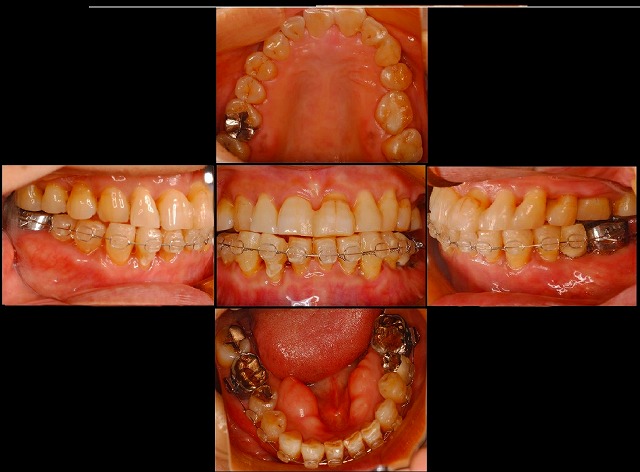

治療中はこんな感じです。

この写真では、インプラント自体が見えませんが、先日の写真の様な感じで入っています。